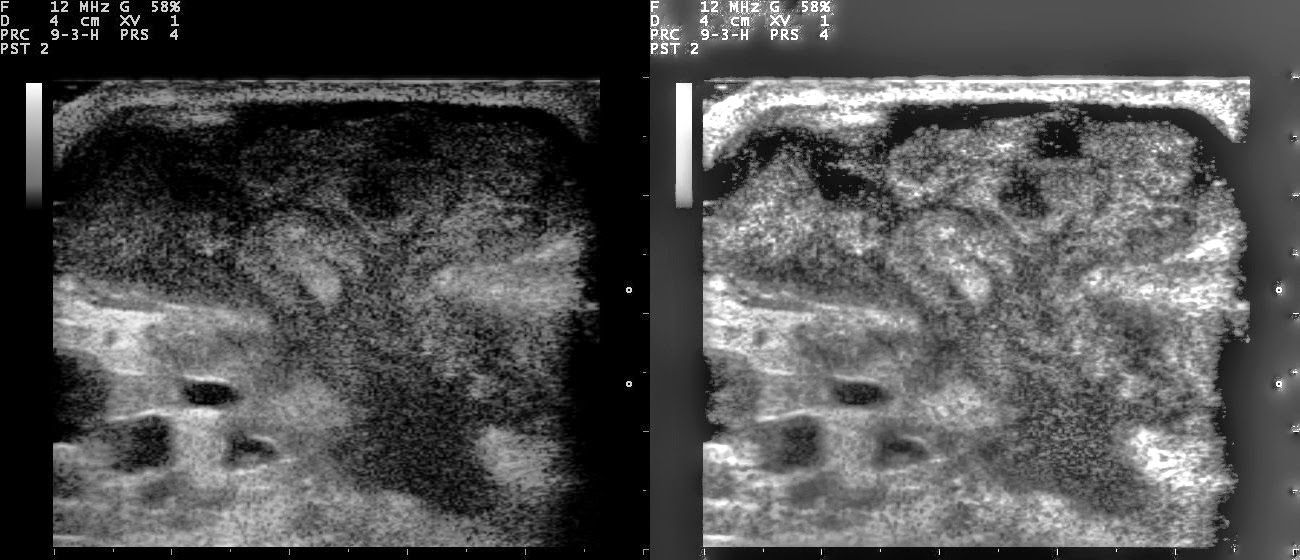

Monitoreo y Seguimiento de Anomalías

El ultrasonido mamario también se utiliza para el seguimiento de afecciones previamente diagnosticadas, como quistes o tumores. Mediante exámenes periódicos, los médicos pueden observar cambios en el tamaño o la forma de las lesiones, lo que les permite detectar cualquier signo de malignidad a tiempo. Esto es crucial para asegurar que no haya un desarrollo de cáncer o cualquier otra afección preocupante.

El ultrasonido mamario es particularmente útil para evaluar la respuesta de los tumores a tratamientos como la quimioterapia o la hormonoterapia antes de la cirugía. Esta técnica permite visualizar cambios en el tamaño y la estructura de las masas tumorales durante el curso del tratamiento. Al proporcionar imágenes detalladas y en tiempo real, el ultrasonido ayuda a los oncólogos a determinar si un tumor está disminuyendo, permanece estable o, en casos menos favorables, está creciendo. Esta información es vital para ajustar los regímenes de tratamiento de manera eficaz y personalizada.

El ultrasonido mamario es particularmente útil para evaluar la respuesta de los tumores a tratamientos como la quimioterapia o la hormonoterapia antes de la cirugía. Esta técnica permite visualizar cambios en el tamaño y la estructura de las masas tumorales durante el curso del tratamiento. Al proporcionar imágenes detalladas y en tiempo real, el ultrasonido ayuda a los oncólogos a determinar si un tumor está disminuyendo, permanece estable o, en casos menos favorables, está creciendo. Esta información es vital para ajustar los regímenes de tratamiento de manera eficaz y personalizada.